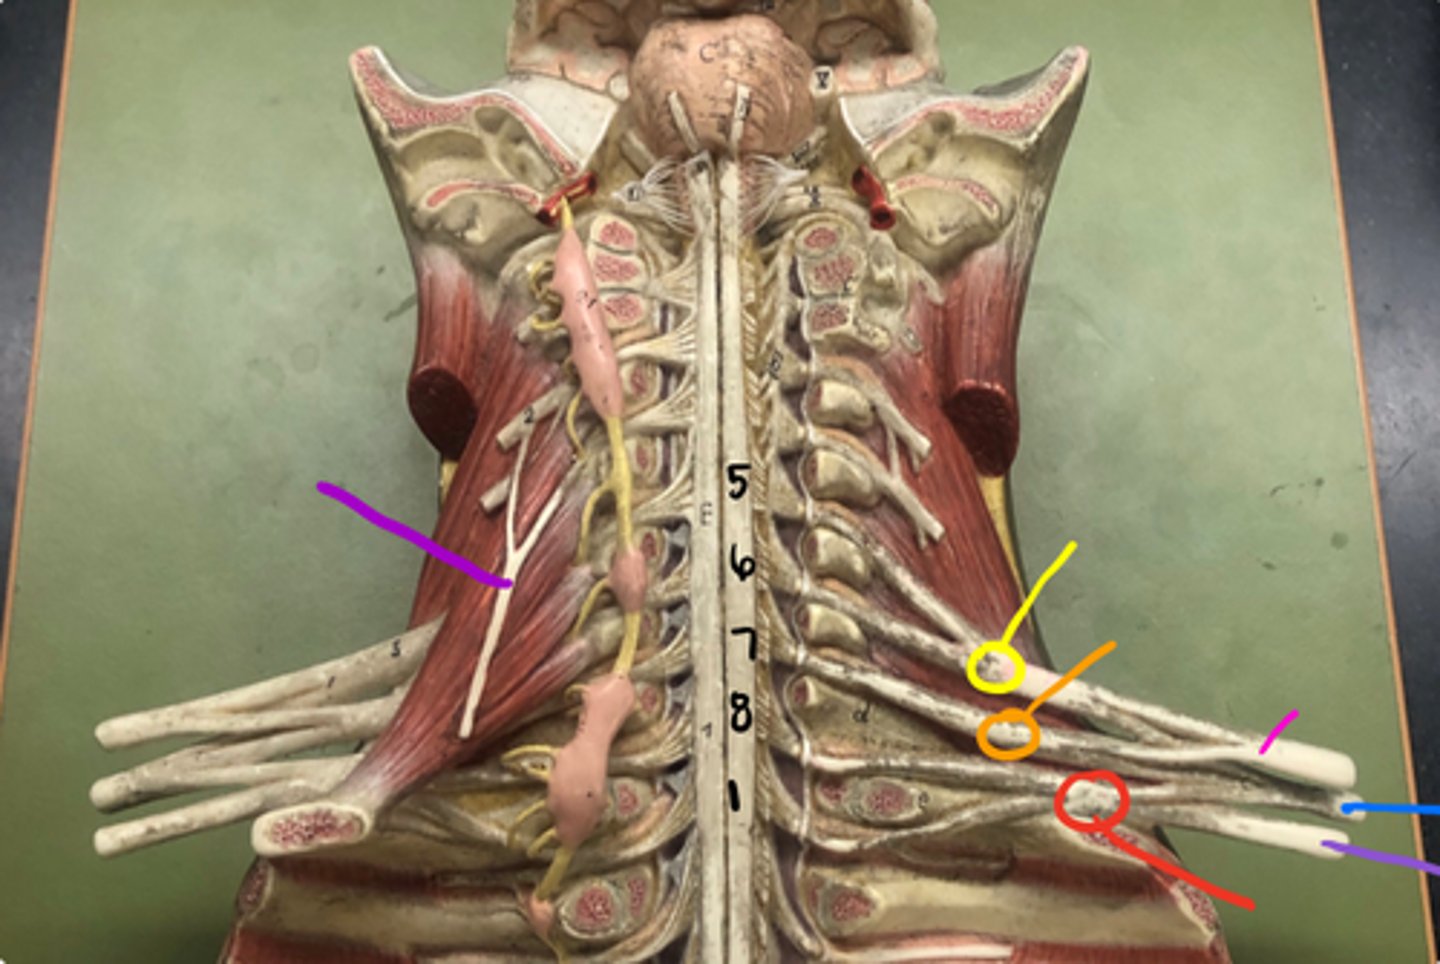

phrenic nerve

neon purple (on neck)

superior trunk

yellow

middle trunk

orange

inferior trunk

red

lateral cord

pink

medial cord

purple

posterior cord

blue